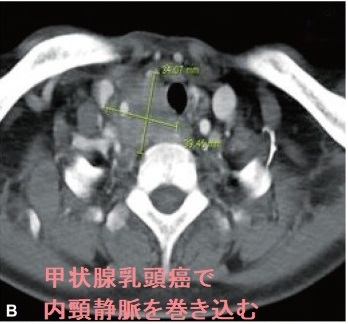

甲状腺癌分化癌(乳頭癌、濾胞癌)の脳転移は遠隔転移の約1%。脳神経症状・けいれんを起こし予後に大きく影響。単発性の場合は原発性脳腫瘍と鑑別できず、摘出後の病理標本で甲状腺乳頭癌・甲状腺癌濾胞癌の脳転移と分かる。最初から放射性ヨウ素(I-131)を取り込んでいれば放射線内・外照射、γナイフ、分子標的薬で治療。下垂体腫瘍で中枢性甲状腺機能低下症(非機能性下垂体腫瘍のほとんどが血清TSH基準値内)。ACTH産生腫瘍は中枢性甲状腺機能低下症を起こし易く、成長ホルモン(GH)産生腫瘍(先端巨大症)は起こし難い(いずれも約50%で血清TSH基準値内)。

甲状腺癌の脳転移は約1%と稀。半数が甲状腺未分化癌、もう半数が甲状腺癌分化癌(乳頭癌、濾胞癌)[J Neurooncol. 2001 Jan;51(1):33-40.]。

甲状腺癌脳転移の診断は、

- 脳CT/MRI